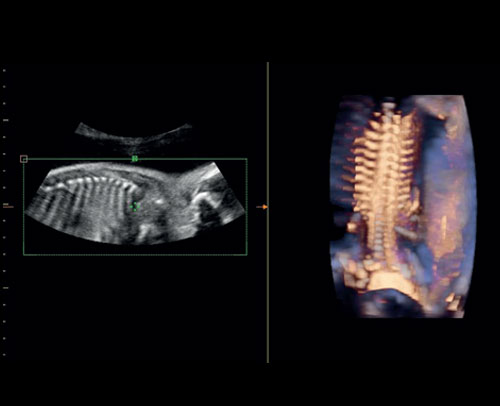

Poloprůhledné vykreslení fetální páteře.